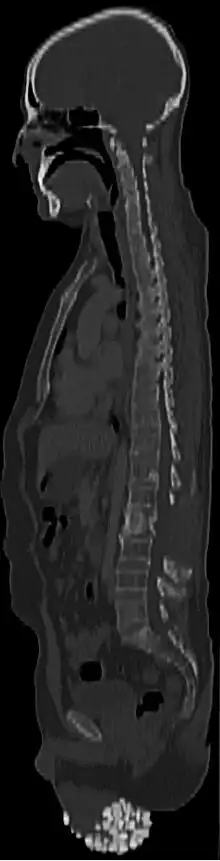

Multiple calcified nodules are seen within the scrotum with normal appearance of the testes on CT